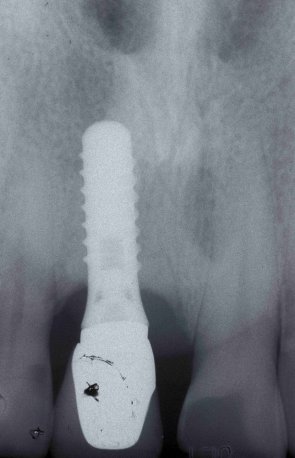

Buonasera sono Carlo di Roma ho 41 anni, vorrei esporre il mio caso:10 anni fa a causa di alcune infezioni ho dovuto togliere le radici dei denti 11-12 con relativi perni monconi e capsule, quindi mi è stato innestato l'osso che per fortuna ha attecchito con 2 impianti. Mentre l'impianto 11 si è osteointegrato bene il 12 ha dato subito dei problemi; infatti è molto sensibile al tatto con la lingua ed in corrispondenza dell'apice si forma una bolla che posso sentire solo io visto che ad occhio nessuno se ne accorge, in quanto in quel punto è visibile solamente una macchiolina rossa. Sicuro che potrete aiutarmi distintamente ringrazio e saluto.

Caro Signor Carlo, la può aiutare il suo Dentista. Io posso solo fare ipotesi come ha fatto giustamente il Dr. De Carli che ha ipotizzato una perimplantite aggiungendo solo che quella "bolla" di cui parla potrebbe essere una fistola o un ascesso in formazione o una infiammazione della gengiva che fa capire che ci siano problemi ossei più profondi! Basta una visita clinica con Rx endorale e sondaggio delle eventuali tasche per fare Diagnosi, Ne parli col suo Dentista!Cordialmente Gustavo Petti, Parodontologia, Implantologia, Gnatologia e Riabilitazione Orale Completa in Casi Clinici Complessi ed Ortodonzia e Pedodonzia la figlia Claudia Petti, in Cagliari.

Gentile paziente, dalla sua descrizione, trattasi molto probabilmente di Perimplantite a carico dell'impianto in zona 12. Sarebbe saggio informare il suo Implantologo, ed effettuare almeno una mini rx-rvg ed un sondaggio parodontale dell'eventuale tasca presente, e verificare l'eventuale possibilità di eliminare il processo dell'infezione che caratterizza la sua situazione clinica. Distinti saluti Dr. Tommaso Giancane